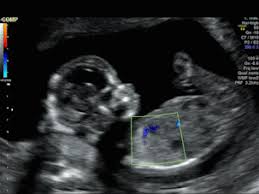

ECOCARDIOGRAFIA FETAL

Evaluación completa del corazón del bebé durante la vida fetal, para detectar o alejar anormalidades en la formación o en la función cardiaca.